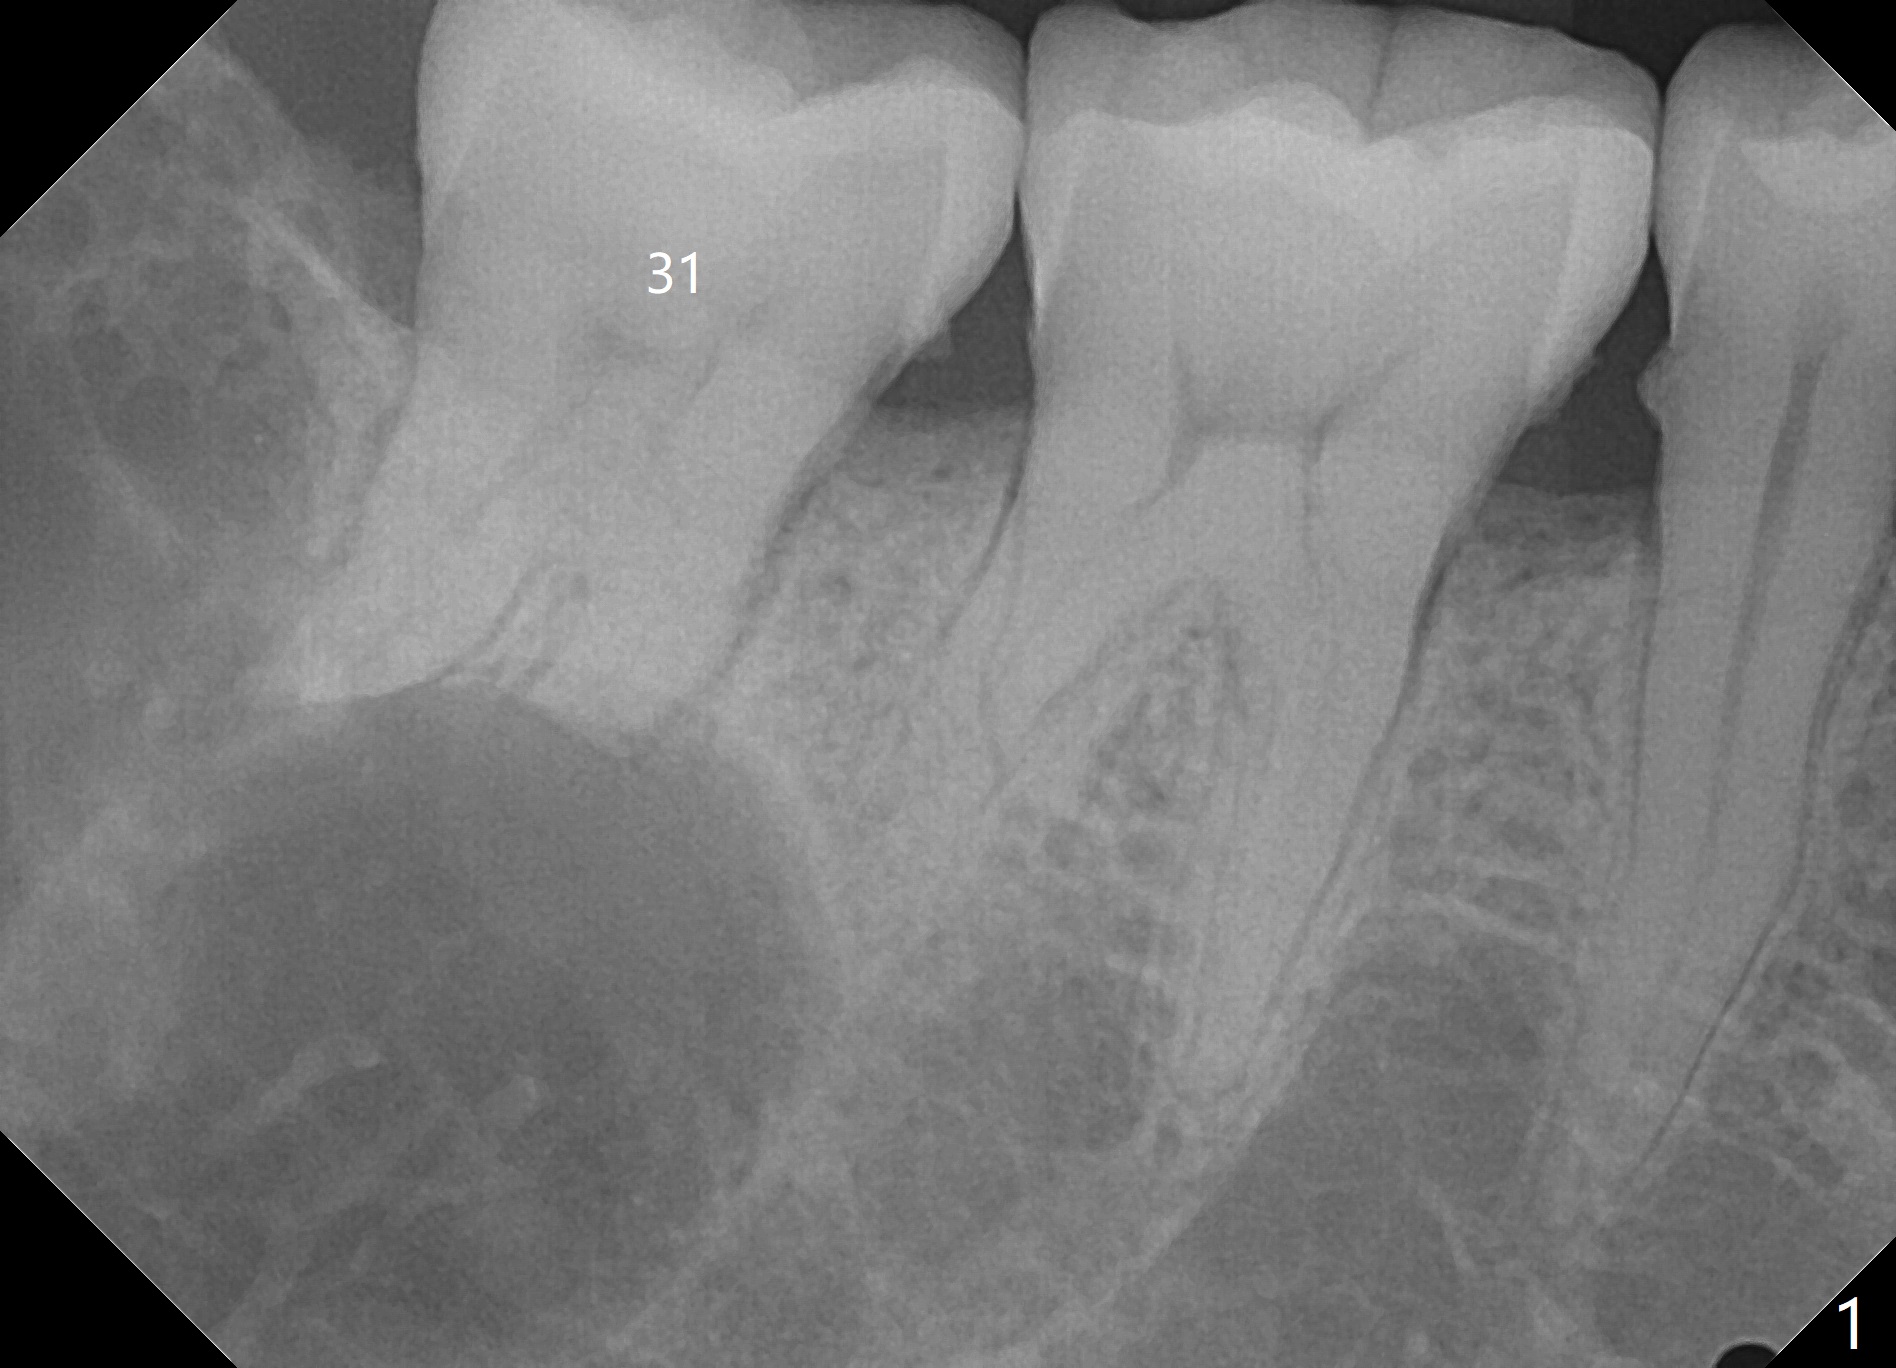

看多房阴影  上方牙槽骨内多个小房(?)  7近中根尖吸收  造釉细胞瘤可能性大

神经应被压迫在颌骨下缘  这X线片上看不到  要看断层  这病例陈平兄是专家

我在日本大学口外20年 清楚他们的治疗方法  这病例还有舌侧骨壁吸收?  向升枝上方浸润(?)  边界不清  也是造釉细胞瘤的特征  记得国内  以前为彻底根治  防止复发 选择截骨方法  在日本  看到相似病例  选择保留颌骨的治疗  看这病例  虽骨吸收区大  但仍有相当骨组织存在 做术中快速切片确诊  切开翻瓣  彻底刮扒干净后 用大圆钻头  尽可能磨除肿瘤区浅层骨面  如需要  用金属板在颊侧下缘固定防骨折(这病例好像不需要)  置皮片引流  缝合关闭  争取I期愈合  关键是术后隔3月  6月  X线复查  如有骨吸收复发  再次做局部手术去除肿瘤组织  这样不截骨  成功可能性较大  当然  最后不能控制  还是要截骨  定期复查是关键  期待听到口外专家的高见[Trick][Trick]

Yaoli @xin wei 下7已受波及  周围骨组织和近中根尖吸收  应拔除  下6好像不在肿瘤骨吸收区内  可保留  术后定期牙片复查  供你参考[Trick][Trick]